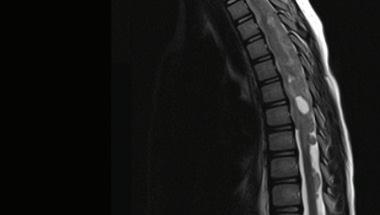

Ependymoma in the spine of an adult patient

Ependymoma in the spine of a pediatric patient